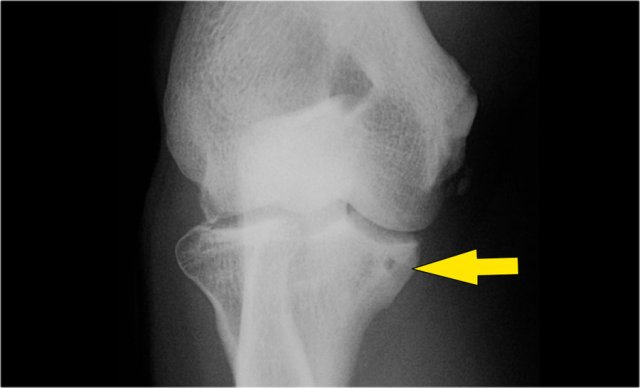

The radiograph is of a 15 year old baseball player with 4 year history of elbow pain and a recent episode of locking.

There is a focal lucency in the capitellum and some fragmntation.

This is typical for a osteochondral lesion of the capitellum and the locking is probably the result of loose bodies.

Continue with the MR...

The MR-arthrogram confirms the osteochondral lesion.

There is gadolinium in between the humerus and the osteochondral lesion which indicates that it is unstable.

If you don't have gadolinium, look for joint fluid undercutting the fragment.

There is a loose body in the posterior recess of the radiocapittelar joint.

Notice also the fragmentation as seen on the axial image.

The osteochondral lesion of the capitellum is typically seen in throwers and gymnasts (11-15 yrs), who get a lot of wrist and elbow problems due to weight bearing.